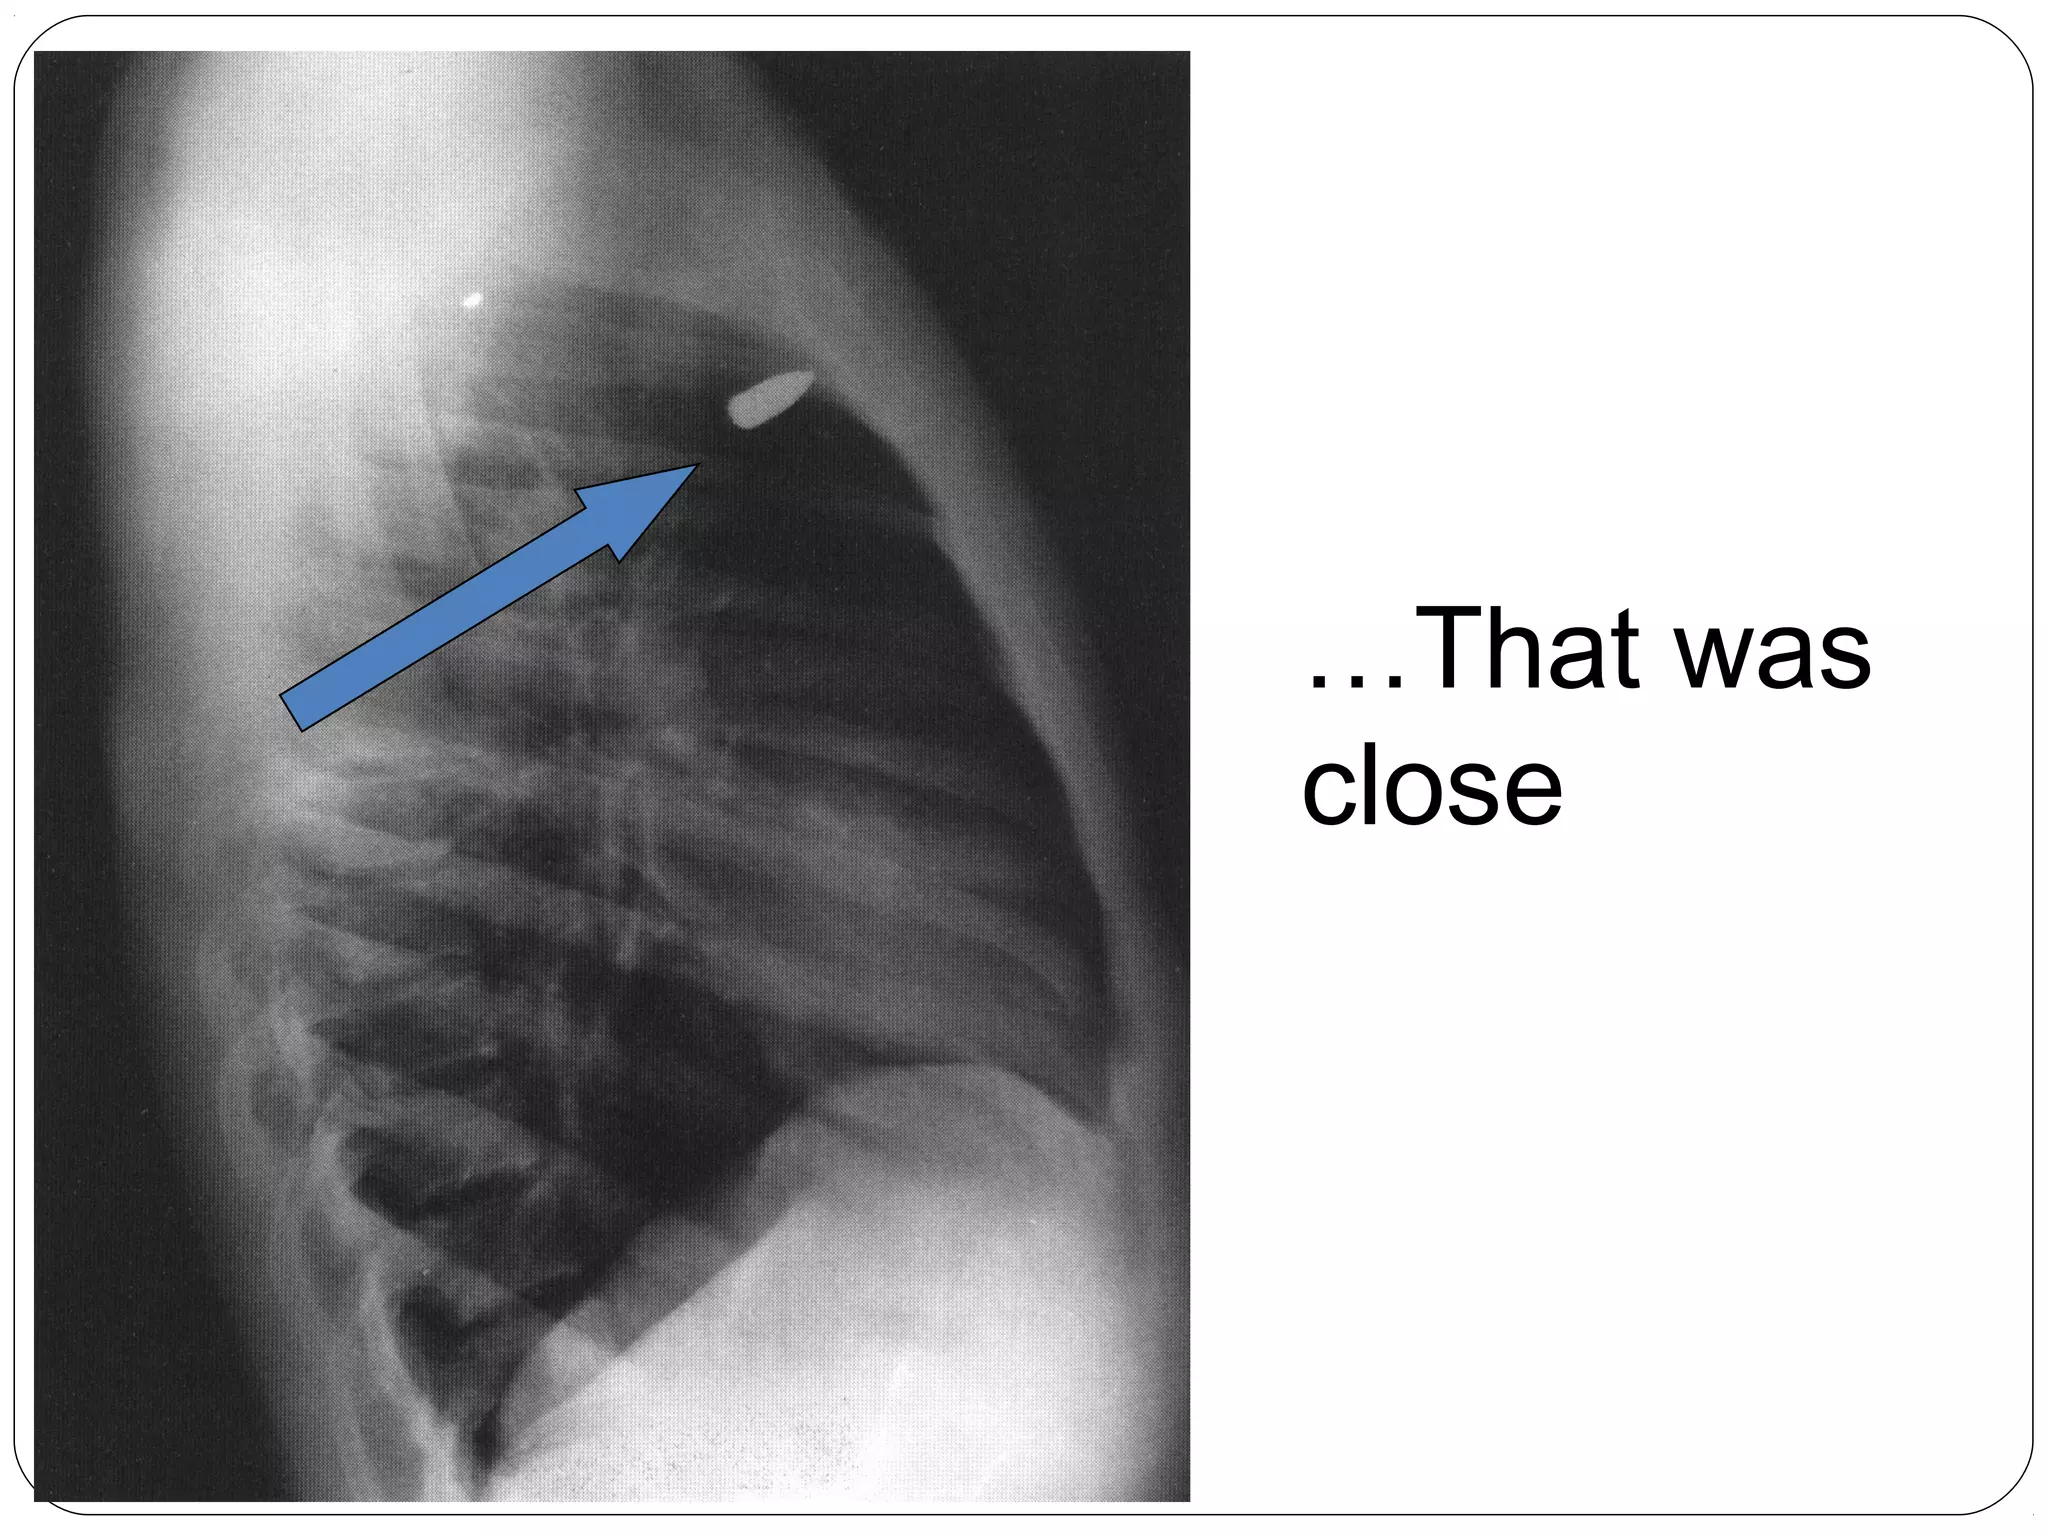

Still Alive?

…That was

close

Bullet can be in

any of these places

(anterior to

posterior at same

level)

1 - spinal cord

2 - trachea

3 – Superior

Vena Cava

4 - aorta